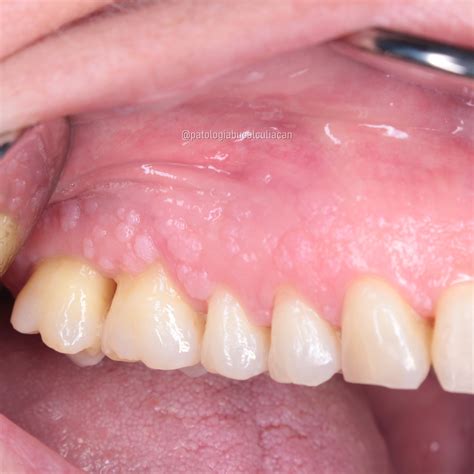

- Papiloma escamoso: es un pequeño tumor -menor a medio centímetro- en forma de coliflor o dactilar que puede aparece en cualquier zona de la cavidad oral.

- Condiloma acuminado: es un pequeño tumor similar en forma al anterior que aparece principalmente en el paladar y la lengua. La forma es de coliflor aplanada, pero con un mayor tamaño que el papiloma escamoso. En ocasiones pueden aparecer varios juntos.

El papiloma escamoso de la mucosa oral es la lesión papilar más frecuente y representa el 2.5% de todas las lesiones de la cavidad oral. Las lesiones clínicas del VPH se observan con mayor frecuencia en el labio superior, labio inferior, frenillo lingual, dorso de la lengua y comisuras. La morfología más comúnmente observada es la de coliflor, aunque también pueden apreciarse otras formas como verrugas vulgares, además de hiperqueratosis o incluso una superficie no queratinizada, con cambios de coloración superficial (normalmente violácea). De acuerdo con las referencias bibliográficas, la mayoría de las veces, se transmite por una práctica sexual orogenital.

Papiloma escamoso en la cavidad oral.

- Apariencia de verruga: Protuberancia pequeña con superficie irregular o con forma de coliflor. Puede ser blanca, rosada o del color de la mucosa circundante.